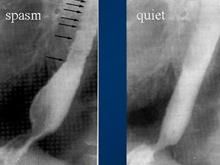

1.X 線檢查 胸部平片無異常發現,食管X 線鋇劑檢查可見蠕動波僅達主動脈弓水平,食管下2/3 為一種異常強烈的、不協調的、非推進性收縮所取代,因而食管腔出現一系列同軸性狹窄,致使食管呈螺鏇狀或串珠狀。但病人症狀的嚴重程度與X 線異常的程度和範圍沒有平行關係,甚至病人毫無症狀,僅在檢查其他疾病時意外地被發現。